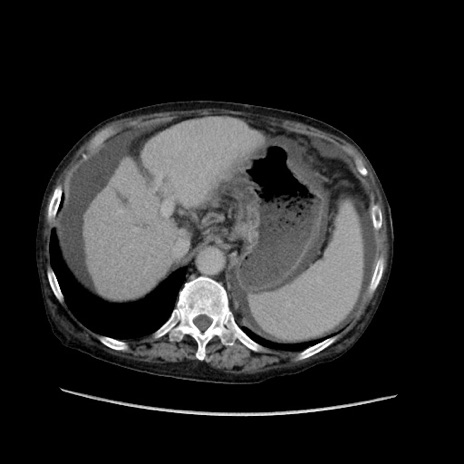

症例31(横断像)

【症例】80歳代 女性

【主訴】腹部膨満感

【現病歴】他院にて肝硬変にてフォロー中。1週間前から便秘、腹部膨満感、臍部腫瘤あり受診となる。

【既往歴】肝硬変

【身体所見】腹部膨隆あり、皮膚変化なし、疼痛なし。

【データ】WBC 4600、CRP 0.25